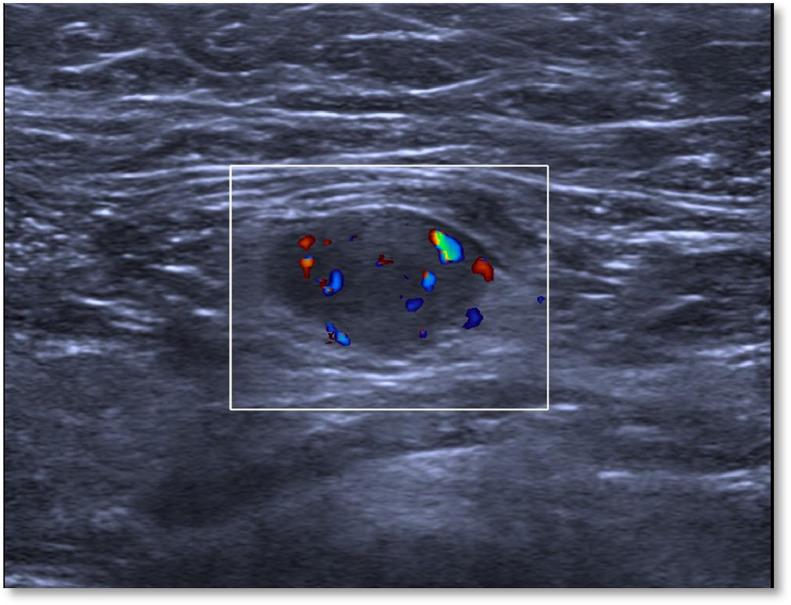

Haemangiomas have been described in many anatomic locations, but occur quite rarely in the breast; although unfrequent, they are the most common benign vascular tumors of the breast. They are comprised in the cathegory of mesenchymal lesions, a spectrum of lesions that arise in the stroma of the breast as defined by WHO. Here we present the case of a breast haemangioma in a 40-years-old woman, with history of a palpable lump in the left breast slowly increasing in size over time. The lesion first underwent diagnostic biopsy in 2018; after a 5-years follow-up with conventional ultrasound, it was studied in 2023 by our group using Contrast Enhanced Ultra-Sound (CEUS) in order to evaluate its vascularization. Basing on our experience, we conclude that in carefully selected cases of histologically proven breast haemangioma, a conservative management with follow-up imaging is safe; CEUS represents a noninvasive method for studying haemangiomas, superior than traditional US thanks to its ability to provide information about vascularity. In those cases with atypical imaging or clinical pathological suspicious characteristics, a complete surgical resection of the vascular tumor is mandatory-in order to exclude the possibility of an underlying angiosarcoma, especially when the lesion measures more than 2 cm.

血管瘤在许多解剖部位均有报道,但在乳腺中极为罕见;尽管不常见,但它们是乳腺最常见的良性血管肿瘤。它们属于间充质病变范畴,是世界卫生组织定义的一类起源于乳腺间质的病变。在此,我们报告一例40岁女性乳腺血管瘤病例,该患者有左乳可触及肿块病史,肿块大小随时间缓慢增大。该病变于2018年首次接受诊断性活检;在进行了5年的传统超声随访后,我们团队于2023年使用对比增强超声(CEUS)对其进行研究,以评估其血管化情况。根据我们的经验,我们得出结论,在经过精心挑选的组织学确诊的乳腺血管瘤病例中,采用随访成像的保守治疗是安全的;CEUS是一种研究血管瘤的非侵入性方法,由于其能够提供有关血管的信息,优于传统超声。在那些具有非典型影像学表现或临床病理可疑特征的病例中,必须对血管肿瘤进行完整的手术切除,以排除潜在血管肉瘤的可能性,尤其是当病变直径超过2 cm时。